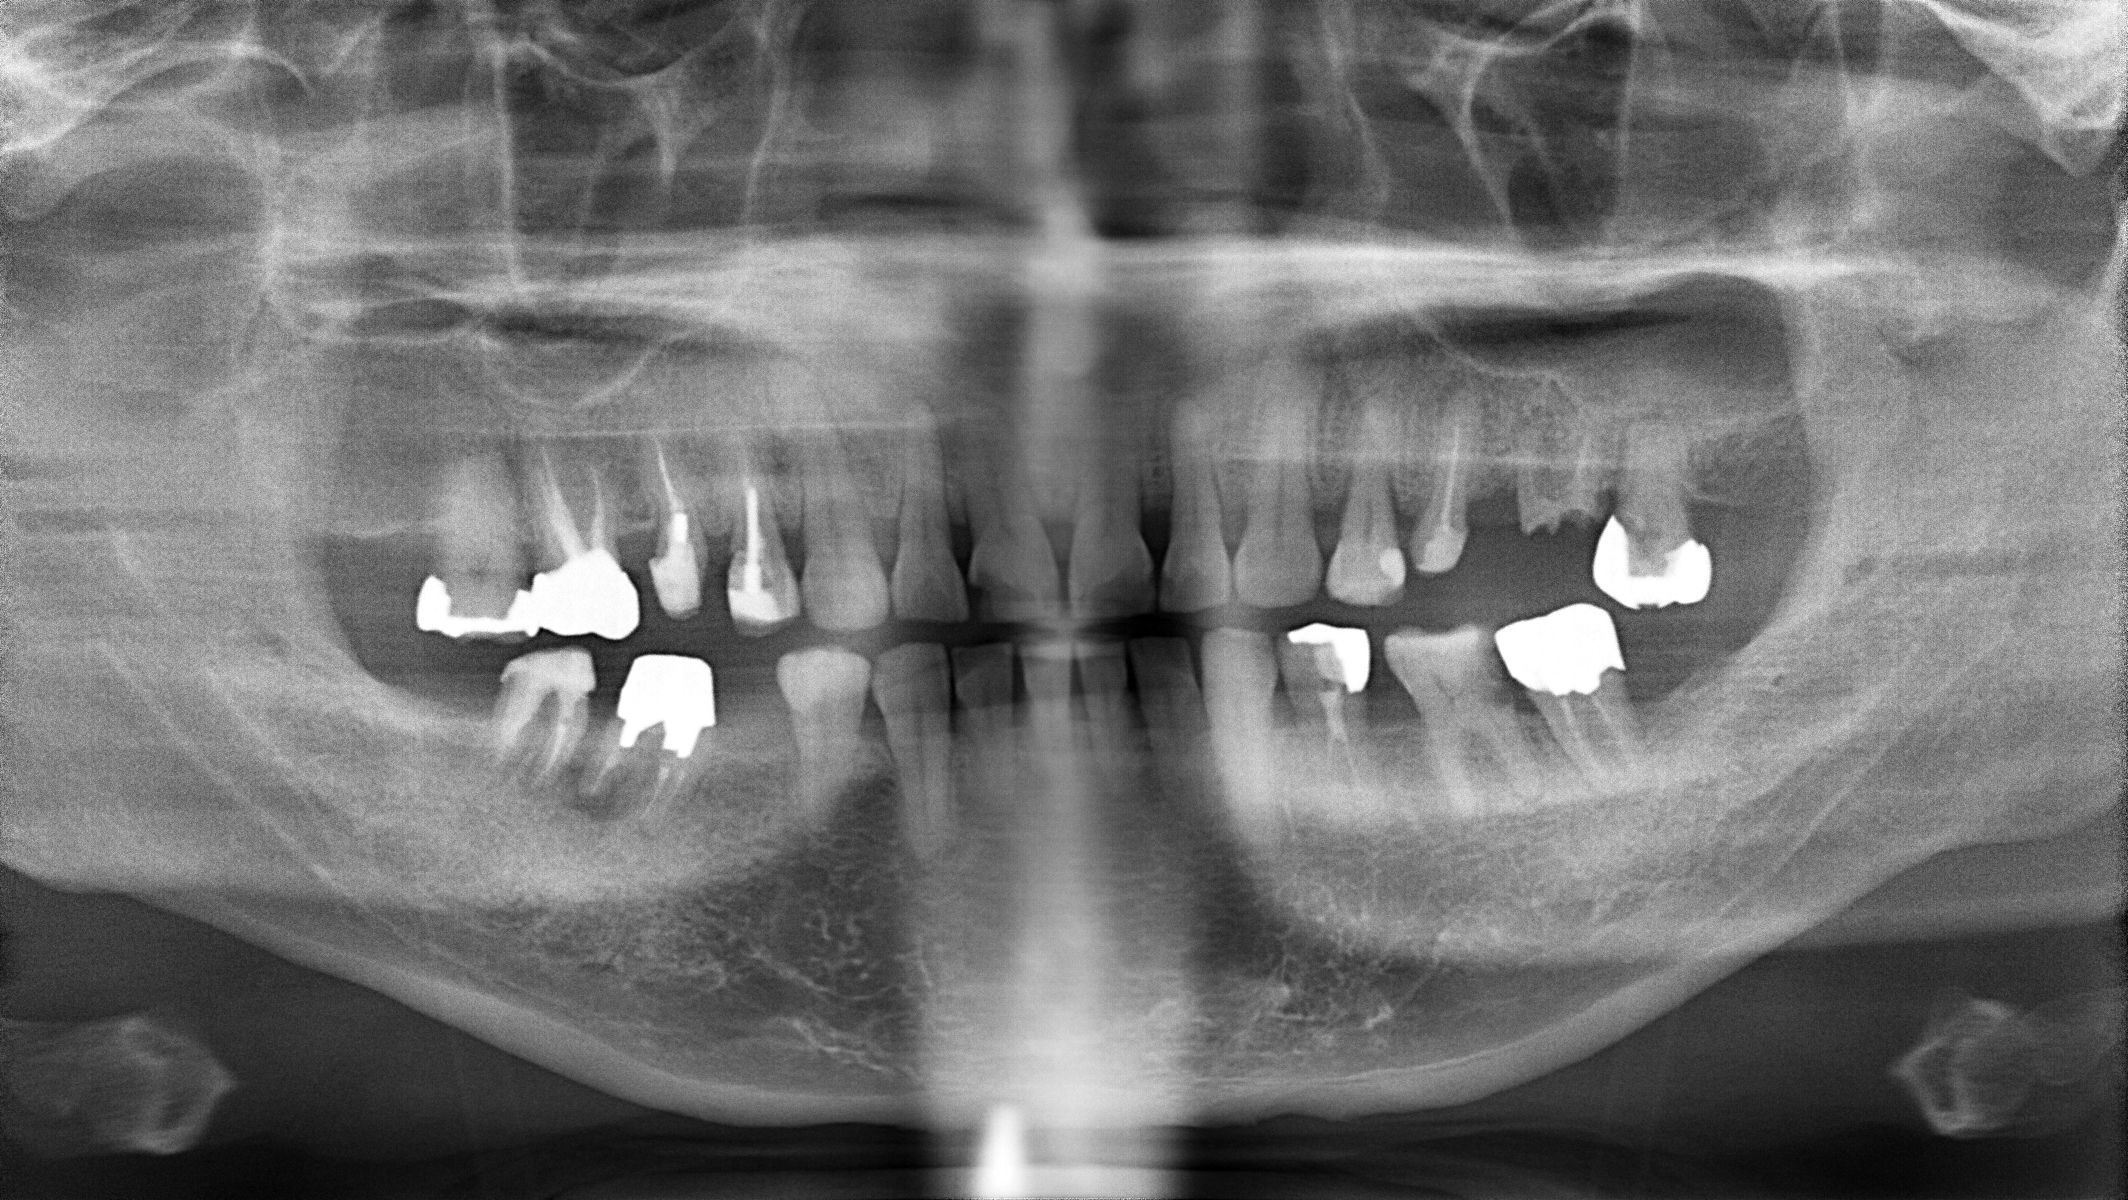

顎関節症の患者さんには、デンタルドック(精密検査)を通して、MRI画像診断とデジタル咬み合わせ検査(T-Scan)を行って治療方針を決定致します。

治療前画像の黄色い矢印の歯が非常に強く当たっていることが、デジタルによる画像からもわかります。そこでその歯を抜歯をすることで顎関節の症状が無くなるのではないか?という予測を立てました。

同時にこの歯は大きな虫歯が全く治療されていない事、また破折を起こしていたため結果的に抜歯という選択肢は、虫歯治療という側面からも整合性をもっています。